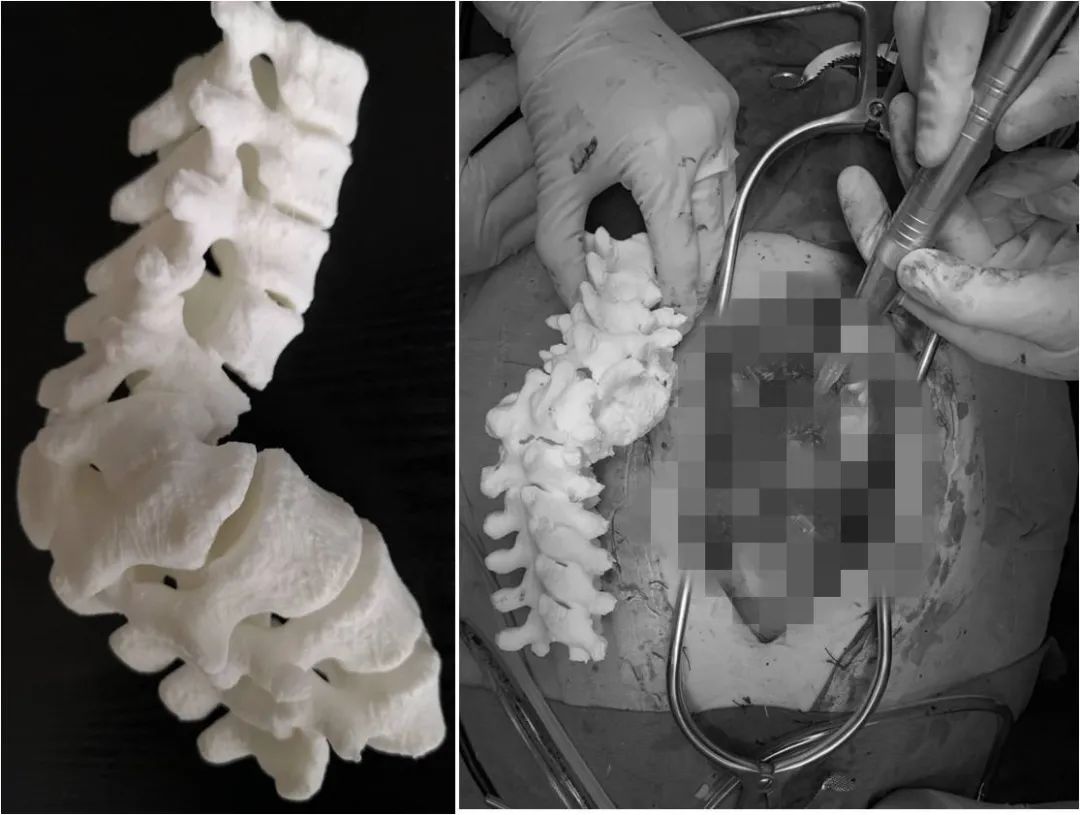

04|3D打印技术

为更精准完成侧弯矫正手术中螺钉的植入,畸形椎体的切除,黄博副教授团队还利用骨科数字化、智能化平台,术前根据CT影像1比1制作胸腰段畸形区域的3D打印模型,一方面组织医疗团队利用模型与拟植入螺钉进行实物比对,提前计算拟植入螺钉的方向、角度,预计使用螺钉的长度和直径;另一方面,利用模型预先设计术中截骨矫形方案,通过多管齐下的措施,进一步提高了手术的精准性和安全性。

06|手术顺利完成